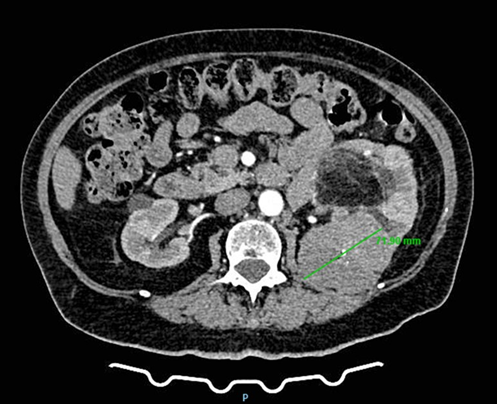

A 78-year-old woman presented to a urology clinic with intermittent left flank discomfort persisting for approximately six months. She denied hematuria, dysuria, or a history of urinary tract infection and renal inflammation. Laboratory findings revealed mild anemia (hemoglobin 109 g/L, hematocrit 0.323 L/L) and normal renal function (creatinine 90 µmol/L, urea 7.7 mmol/L). Her medical history was notable for hypertension and well-controlled type 2 diabetes mellitus managed with oral hypoglycemics. On physical examination, a palpable mass was detected in the left flank and hemiabdomen. Abdominal ultrasonography revealed a poorly defined lesion within the left kidney, approximately 90 × 60 mm in size. Contrast-enhanced CT of the thorax, abdomen, and pelvis demonstrated multiple small cystic lesions up to 25 mm in the left kidney, along with two major solid masses of clinical significance. A lobulated mass at the upper pole (67 × 60 mm) exhibited central calcifications and contrast enhancement consistent with RCC (Figure 1). A second, well-circumscribed lipomatous lesion (110 × 100 mm) was identified at the lower pole and renal hilum (Figure 2), causing compression and deformation of the collecting system without invasion, initially interpreted as an angiomyolipoma. The renal vein demonstrated a retroaortic course, a relevant anatomic variation for surgical planning. After multidisciplinary evaluation including urologists, oncologists, abdominal surgeons, and interventional radiologists, preoperative embolization of the left renal artery was recommended, followed by radical nephrectomy.

Figure 1: CT scan demonstrating a left renal mass with radiologic features of clear cell renal carcinoma.